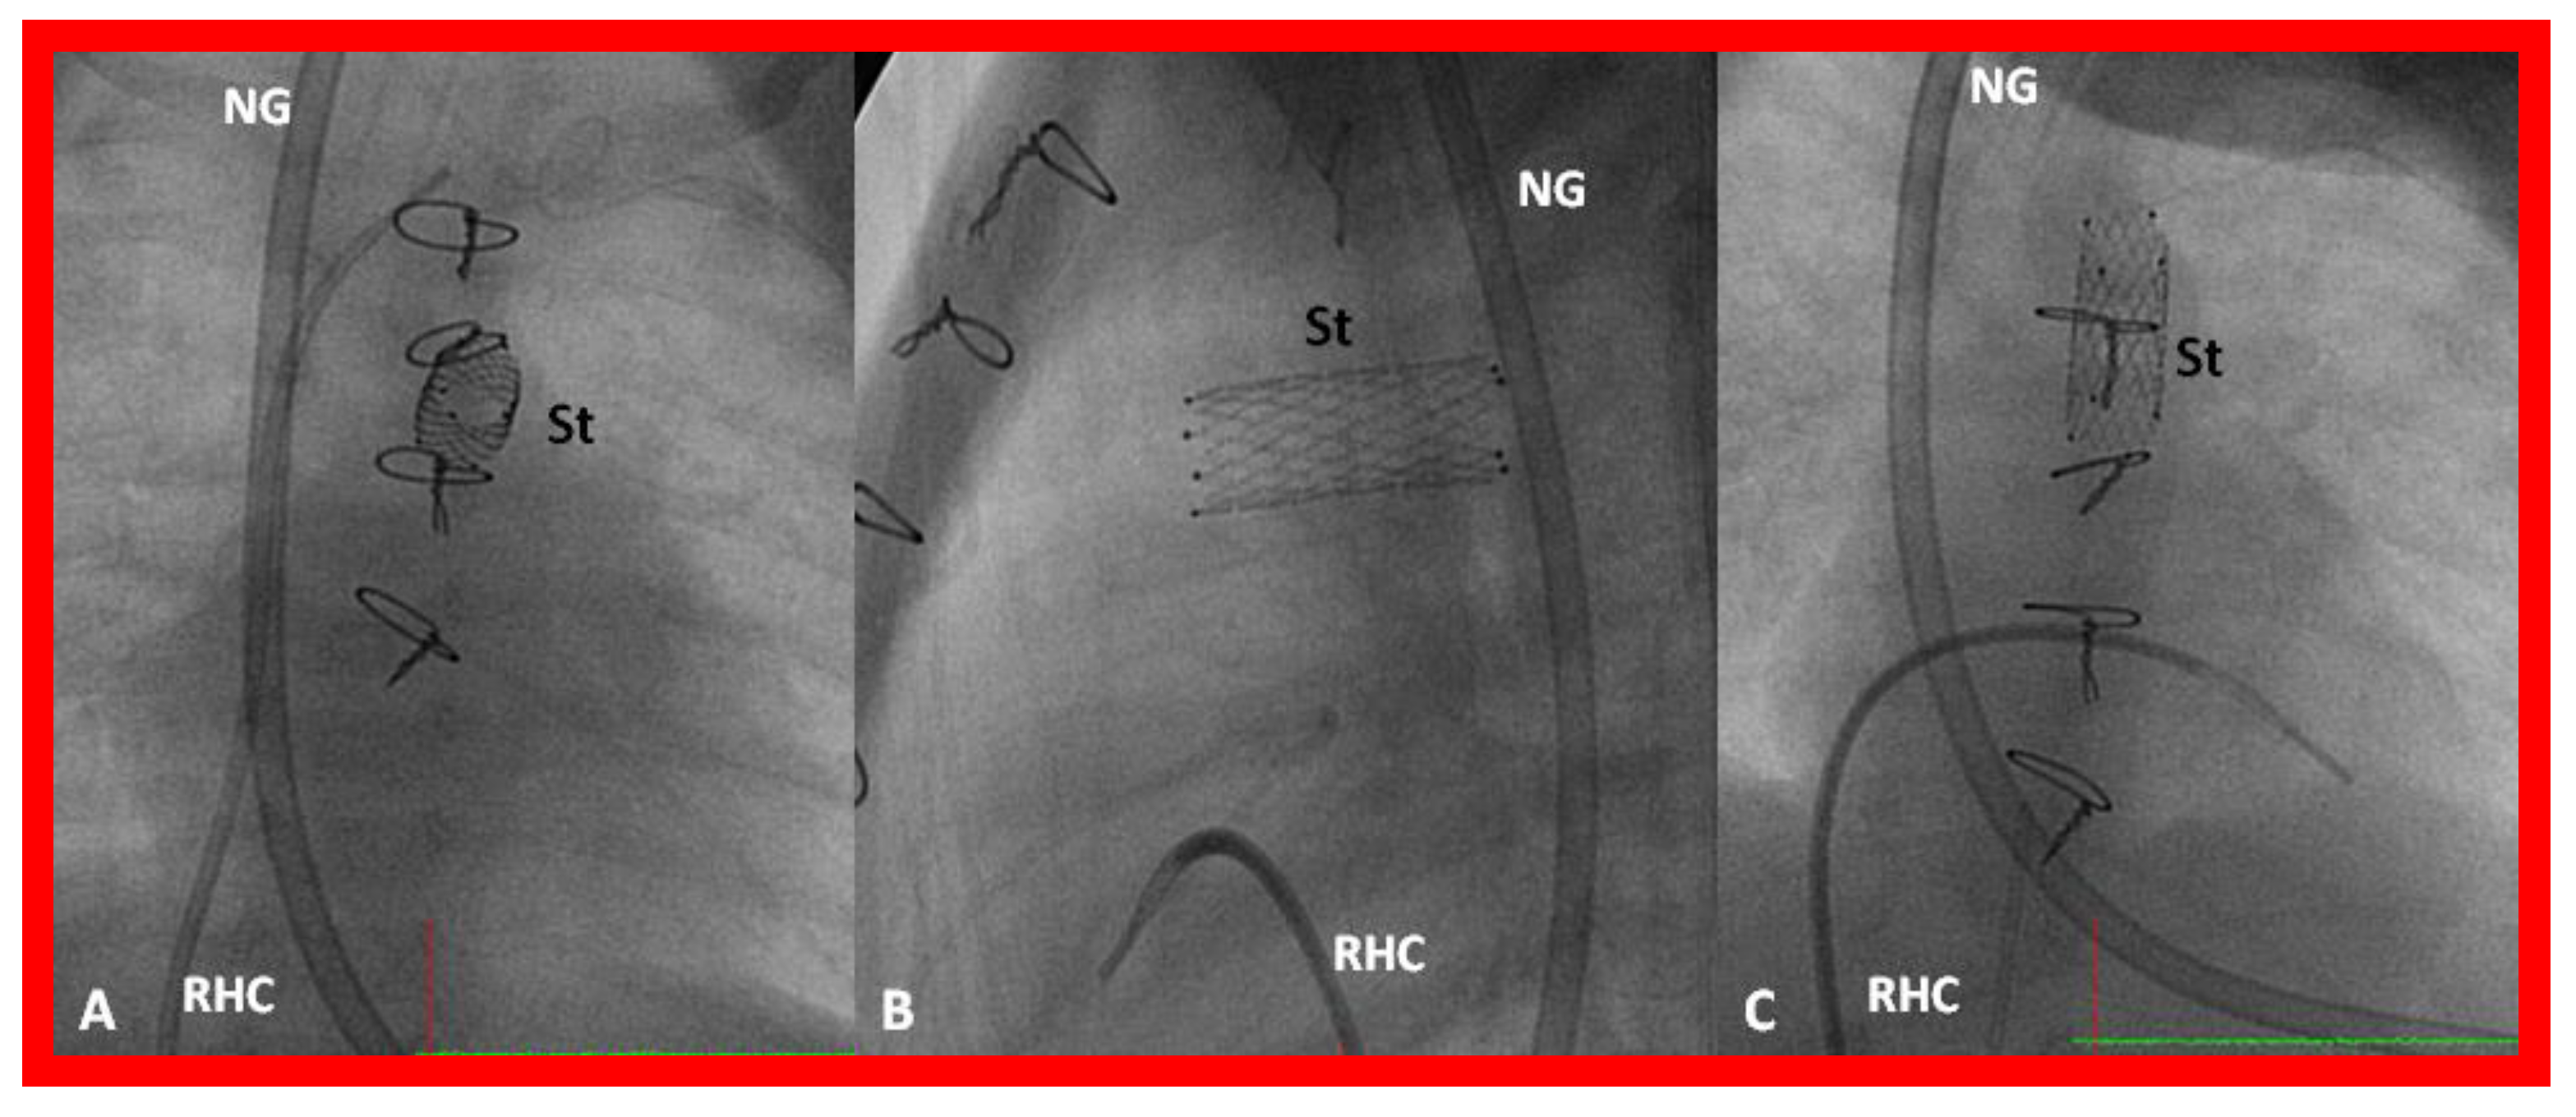

Figure 30.

Selected cine frames in postero-anterior (A), lateral (B) and sitting-up (C) views, showing the position of a stent (St) placed within the ductus via a purse-string suture in the pulmonary artery in a premature neonate with hypoplastic left heart syndrome during a hybrid procedure. NG, naso-gastric tube; RHC, right heart catheter. Sternal wires are seen. Reproduced from Reference [58].

Figure 31.

Selected cine frames in sitting-up (A) and right anterior oblique (B) views from a right ventricular (RV) angiogram, demonstrating the position of a stent (STENT) placed within the ductus via a purse-string suture in the pulmonary artery during a hybrid procedure, in a premature infant with hypoplastic left heart syndrome shown in Figure 30. Note the opacification of the descending aorta (DAo) via the stent. Bands placed during the hybrid procedure around the right (RPA) (in B) and left (LPA) (in A) pulmonary arteries are seen. ARCH, aortic arch opacified retrogradely via the STENT. NG, naso-gastric tube.